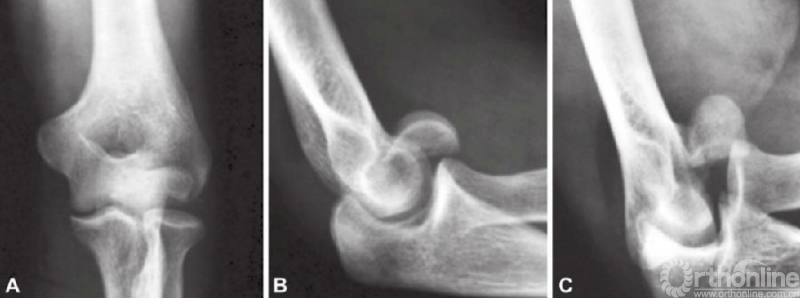

冠状突骨折应拍摄肘关节正位(AP)、侧位片,如果有需要,还应该拍斜位片以明确是否有骨损伤。斜位片对轻微移位的骨折尤为重要,因为肘关节侧位片上桡骨小头和尺骨冠突影重叠,因此冠状突骨折容易和桡骨小头骨折混淆。

为避免这个情况,Greenspan和Norman介绍了肱桡位片(图6和图7)。这个位置可以把桡骨头及冠突区分开,可以提供清晰的冠突、桡骨头、肱桡关节和上尺桡关节。有时普通的X线片难以提供完全确切的诊断依据,这就需要行CT扫描或MRI检查。

图6 肱桡位片拍摄方法

图7 A~C肱桡位片正位片上看似乎是单纯的肱骨小头骨折,事实上在侧位片和肱桡位片上可以看到合并有冠状突骨折